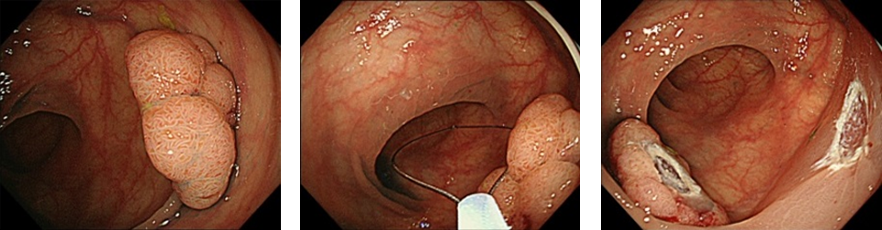

大腸ポリープを内視鏡により切除することは、大腸がんの発生率を低下させます。当院ではポリープの種類、サイズに応じて外来、入院でのポリープ切除術を施行しています。

大型生検鉗子で切除

スネアで切除

高周波通電による切除